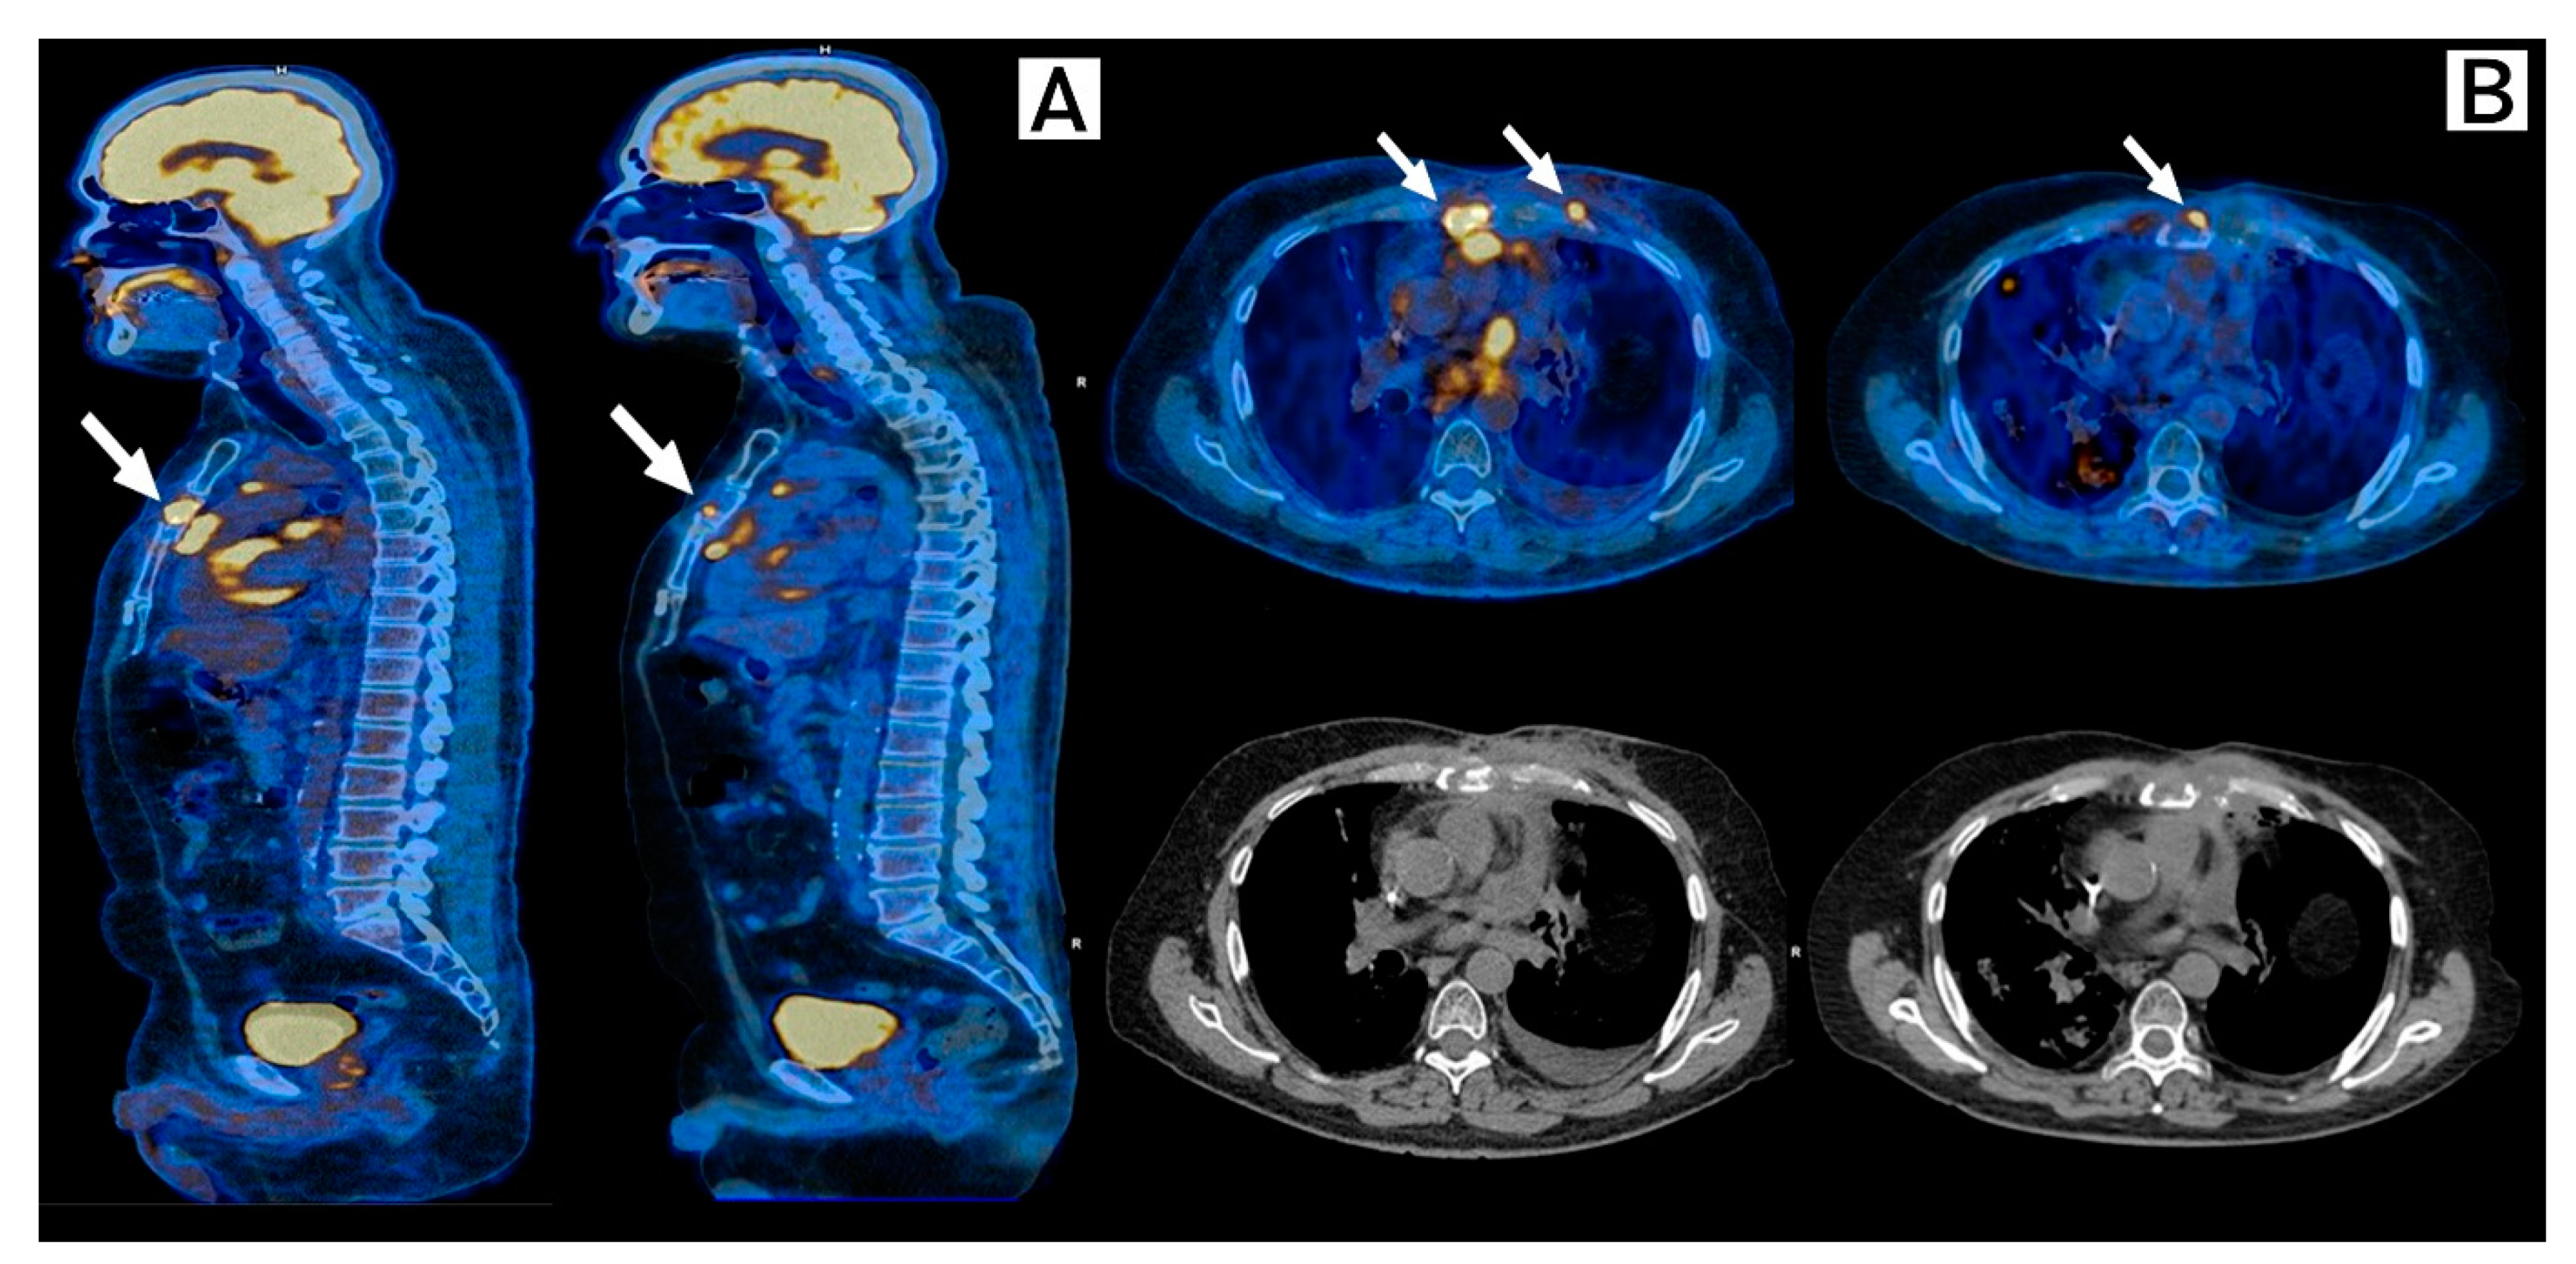

In November 2020, new images documented a new anterior chest wall tumor and disease progression to the sternum and pericardium. Considering multiple prior lines of treatment including chemotherapy and immunotherapy, a good performance status (ECOG 1), case reports and a phase II trial of the benefit of CDK4/6i Palbociclib in tumors which harbor somatic alterations in CDKN2A and, after informed consent, off-label Abemaciclib was started on December 2020. Re-staging PET-CT on February 2021, after 8 weeks of treatment with good tolerance, showed stable disease with metabolic response in the pericardial lesion, costochondral joints, and sternum (Figure 2).

Figure 2.

Response to Abemaciclib in the sternum and costochondral lesions. FDG-PET-Scan, Baseline (left) and 8 weeks after (right) after initiation of Abemaciclib. (A) Sagittal plane and (B) Transversal plane. Arrows show stable disease and complete metabolic resolution of costochondral lesions and near-complete metabolic response of the sternal lesion when compared with prior scans.